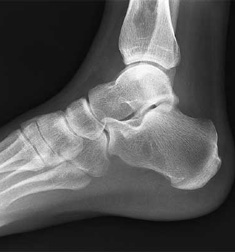

Foot and Ankle X-Ray

Support the MASTAF Study Group's Research

As part of the MASTAF Study Group, we are looking to find answers to difficult questions related to the surgical treatment of patients with ankle and foot injuries.

A variety of studies will be conducted within this MASTAF project, as hundreds of data points are being collected. The ability to bring data together from multiple centers empowers our group study to make conclusions that a single surgeon experience cannot produce.